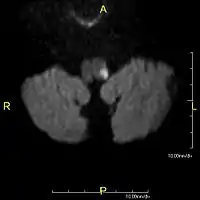

- Каудальна частина (лат. pars caudalis) — ділянка ядра, що розташована найближче до спинного мозку. Є ключової ділянкою у сприйнятті больових та температурних подразників від шкіри обличчя. Інформація аналізується за певним топічним принципом: центральні ділянки обличчя аналізуються більш рострально в ядрі (ближче до кінцевого мозку), а периферичні — дорсально (ближче до спинного мозку). На обличчі та чи інша ділянка має вигляд дуги або підкови і називається зоною Зельдера.[36][35][33][21]